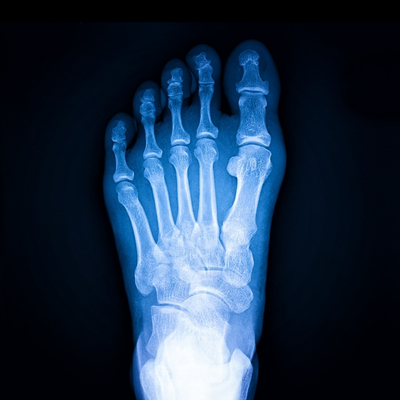

Very simply put, an X-ray takes a snapshot that captures a moment in time. This ‘photo’ shows bones and dense structures to help detect fractures and infections.

X-rays are relatively fast and straightforward to take, just like having your passport photo done. Our highly trained radiographer will help you sit, stand or lie in the correct position. They’ll ask you to keep still and then take the image.